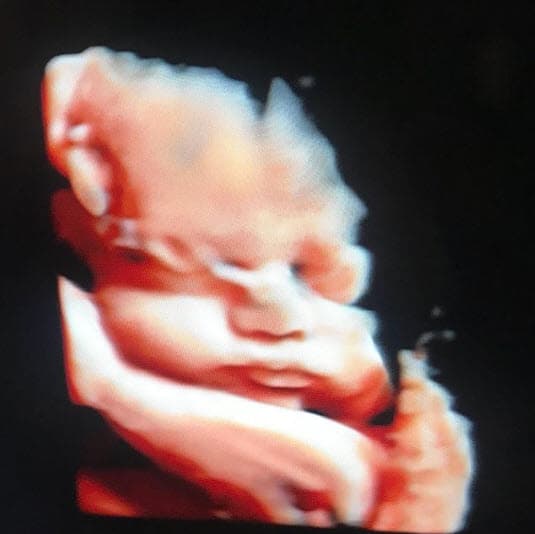

También mostraron el primer ultrasonido de Leonardo en redes sociales.

Instagram @plutarcohaza

Por el mismo medio, revelaron el nombre que habían elegido para su hijo. Fue en diciembre pasado cuando, con una imagen del ultrasonido del bebé, que Plutarco escribió:

“¡Listos para recibir a Leonardo!”.